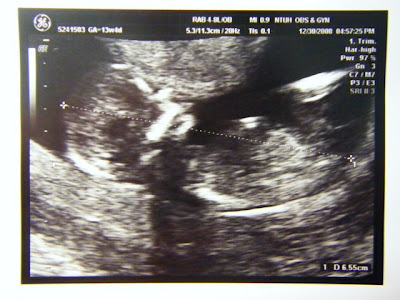

聽到我的心跳了嗎?

這是12週多時的超音波照,從十週之後就已經可以透過儀器聽得到小小飛的心跳了喔。